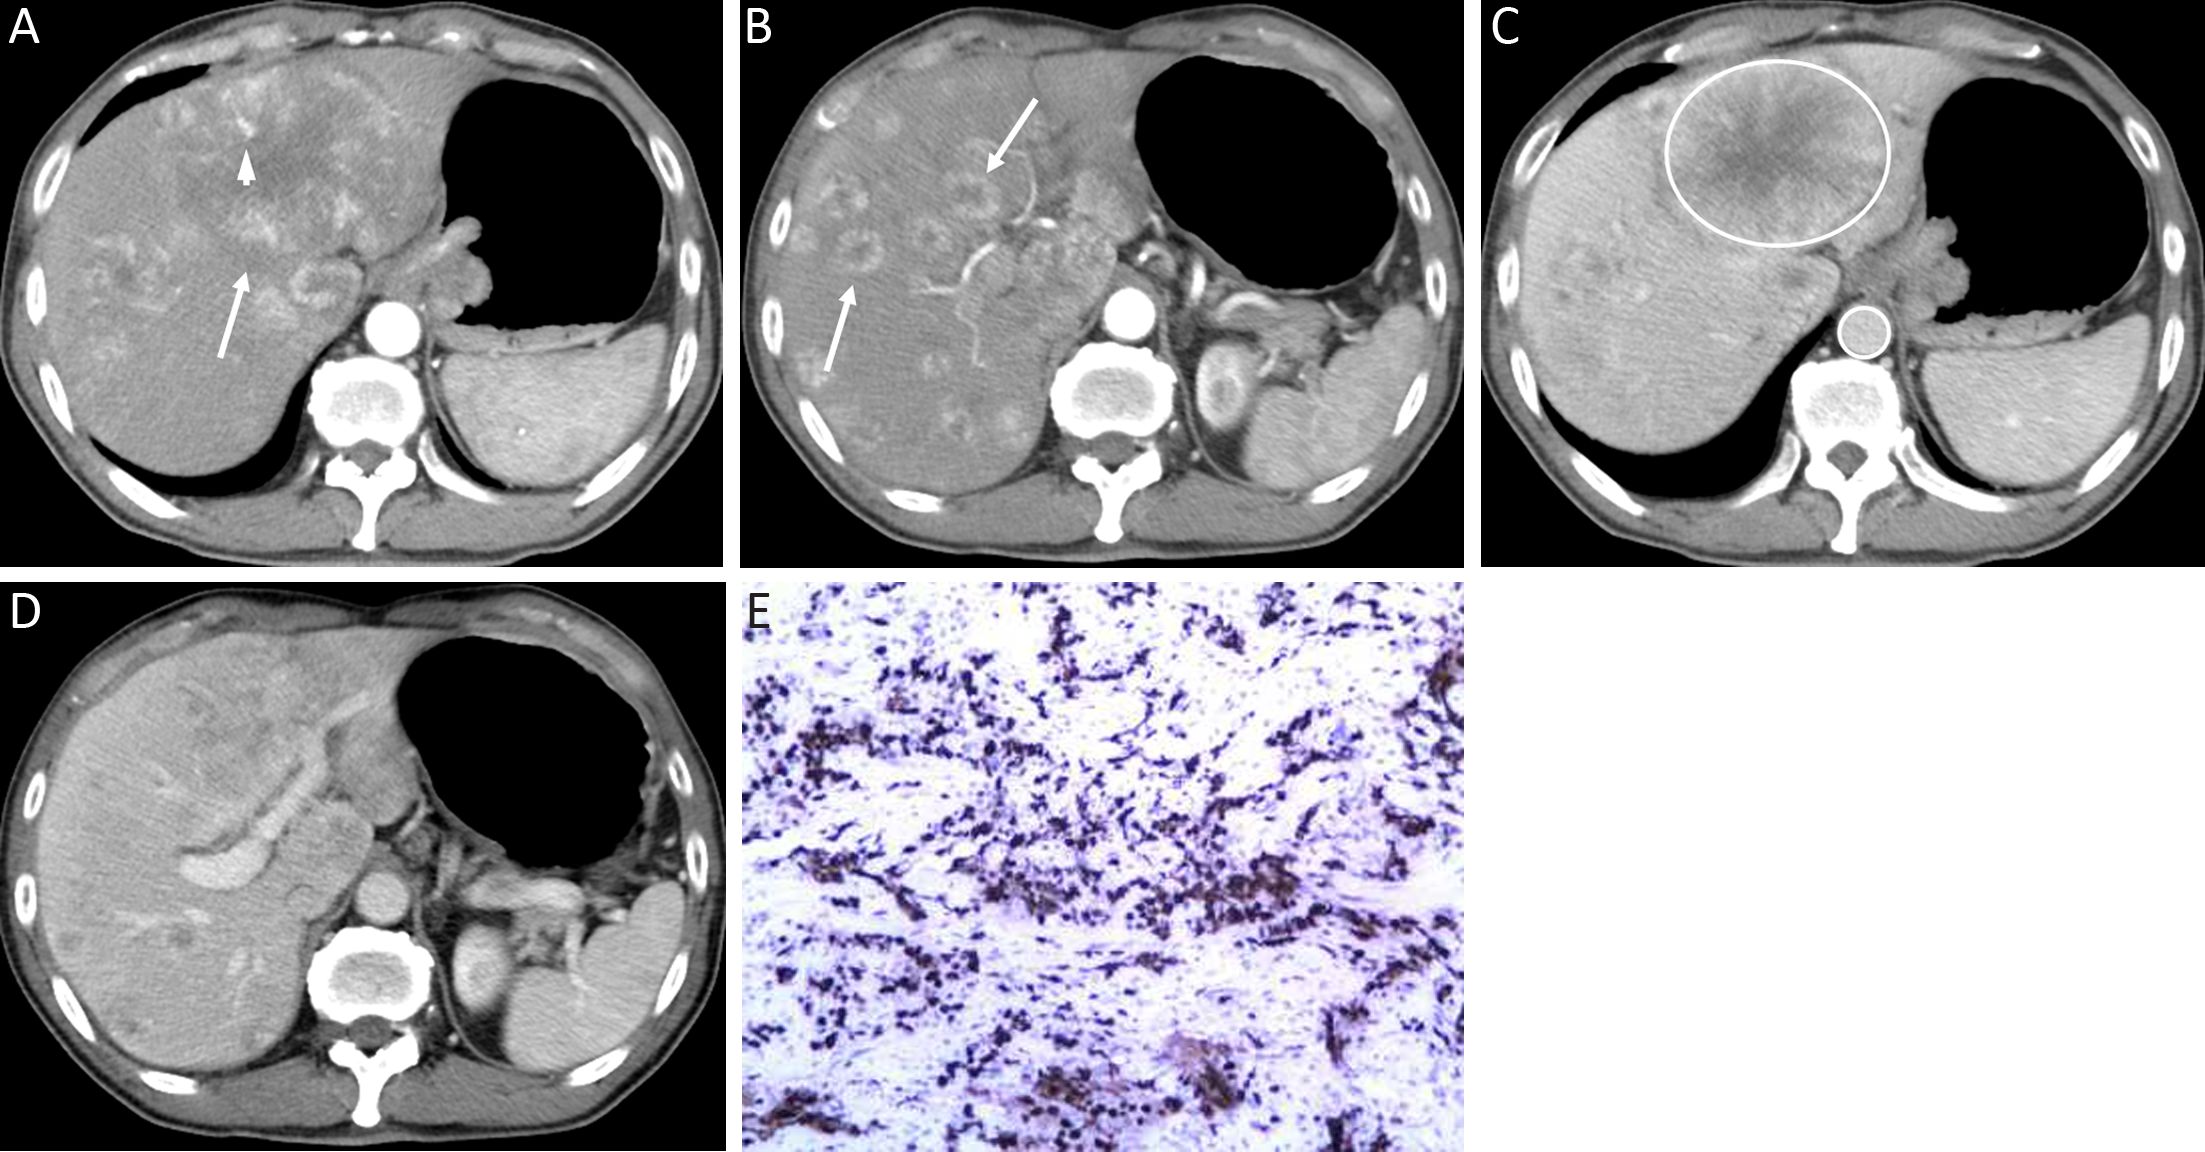

The qualitative image analyses of LMs of well- and poorly-differentiated GEP-NENs are summarized in Table 2. The distribution and shape of tumors were not significantly different between the two groups (P=0.761 and 0.508). All the LMs of GEP-NENs were mainly diffused with a round-oval shape. More feeding arteries and intratumoral neovascularity were found in LMs of poorly-differentiated GEP-NENs than in LMs of well-differentiated GEP-NENs (P=0.005 and 0.003). With regard to the enhancement area, there was no significant difference (P=0.050), and the enhancement pattern was not significantly different (P=0.477). Lymphadenopathy was statistically significant in differentiating LMs of well-differentiated GEP-NENs from poorly-differentiated GEP-NENs (P<0.001), with lymphadenopathy occurring more often in poorly-differentiated GEP-NENs. Representative cases are shown in Figures 2 and 3.

Difference of quantitative CT parameters between LMs of well-differentiated and poorly-differentiated GEP-NENs

The quantitative CT parameters are shown in Table 3. LMs of well-differentiated GEP-NENs were more enhanced than those of poorly-differentiated GEP-NENs. T-A/AP, T-L/AP, and T-A/PVP were significantly higher in LMs of well-differentiated GEP-NENs (all P<0.05) shown by the t-test. Only T-L/PVP was not significantly different between the two groups (P=0.054).

The use of dynamic enhanced CT has been described as being helpful in differentiating tumor pathologic grade in GEP-NENs. Some studies of pancreatic NENs have shown that well-differentiated tumors are more vascularized than poorly-differentiated tumors on enhanced CT (16-18). In our study, a higher degree of enhancement was found in LMs of well-differentiated GEP-NENs both in the hepatic arterial and portal venous phases compared to poorly-differentiated GEP-NENs. In contrast, a MRI study (19) showed a higher degree of early hepatic arterial enhancement in Grade 2 and 3 LMs vs. Grade 1 LMs. This discrepancy may be partly due to different study populations (primary site of GEP vs. whole body) and different grouping methods (Grade 1 and 2 to Grade 3 vs. Grade 1 to Grade 2 and 3). Further study may be required to investigate the relationship between dynamic enhanced CT quantitative parameters and pathologic grading of NEN LMs from a single primary site.

In this study, LMs of poorly-differentiated GEP-NENs showed more feeding arteries and intratumoral neovascularity than LMs of well-differentiated GEP-NENs. Similar results have not been reported in previous studies. A possible explanation for the higher incidence of feeding arteries and intratumoral vessels in LMs of poorly-differentiated GEP-NENs could be that those vessels may represent both an increase in the number and dilation of the vascular architecture, and may correlate with the high proliferation rate of the tumor, which grows rapidly and thus requires more blood supply (20). The relationship between the growth and presence of vessels within and surrounding LMs was reported in an experimental study (21). The results showed that, in a murine model, larger LMs had large vessels surrounding and within the lesions in the late growth stage of NEN LMs. Our results may indicate that the existence of tumor vessels in LMs of GEP-NENs also correlate with pathologic classification.

We found that lymphadenopathy was present in 81.2% of patients with poorly-differentiated GEP-NENs, compared with 27.3% of patients with well-differentiated GEP-NENs. These results were similar to those in the study by Kim et al. (11), which showed that the majority of poorly-differentiated gastric NENs had metastatic lymph nodes (94.4%) while metastatic lymph nodes were noted in 22.2% of patients with well-differentiated gastric NENs. In another study by Kim et al. (22), poorly-differentiated NENs of the gallbladder showed larger lymph node metastases than adenocarcinoma (4.62 cm vs. 2.41 cm). The increasing presence of lymphadenopathy also demonstrates that the biologic behavior of poorly-differentiated NENs is highly aggressive, whereas the behavior of well-differentiated NENs is often indolent. Our results are in line with these results as lymphadenopathy was one of the predictors for LMs of poorly-differentiated GEP-NENs in our study [Exp(B)=2.908].